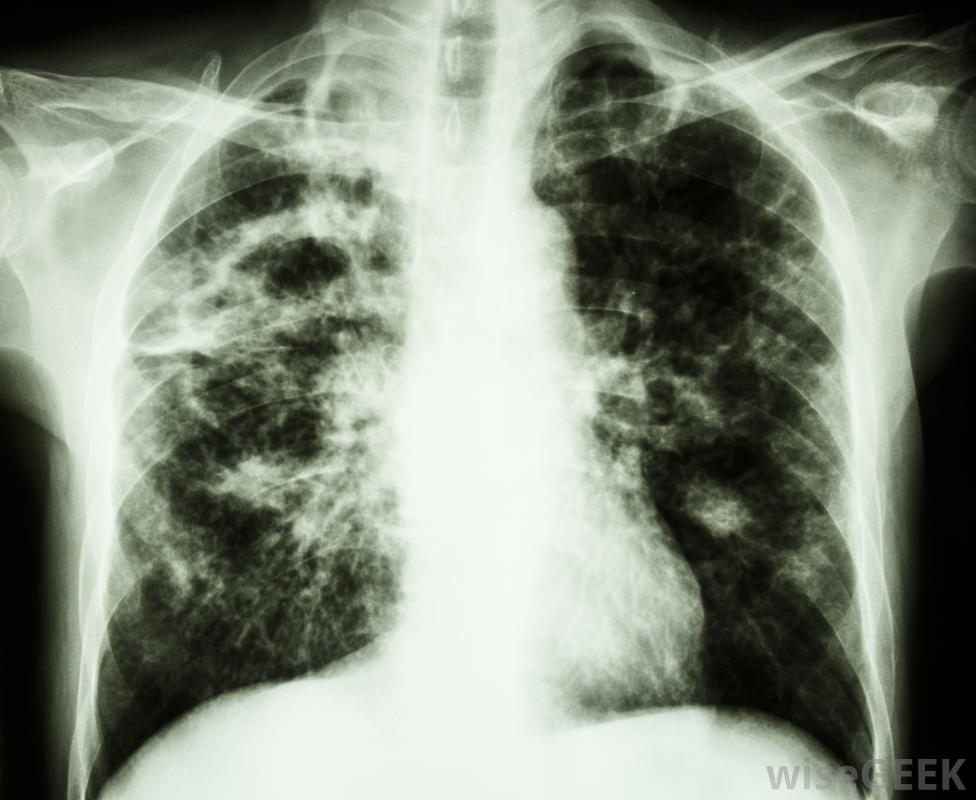

结核病通常影响肺部并引起盗汗和发烧。

一种臭名昭著的需氧菌是结核分枝杆菌,肺结核引起肺结核的有机体。肺结核是一种或多种结核分枝杆菌被吸入并在宿主体内成功繁殖,特别是在肺部。由于结核杆菌是有氧的,嗜氧的,免疫系统有限的个体的肺是一个好客的栖息地,大多数健康人都有免疫系统,可以防止这些需氧菌在体内停留并引起感染

肺结核是一种需氧菌,往往在肺部富氧的环境中茁壮成长。